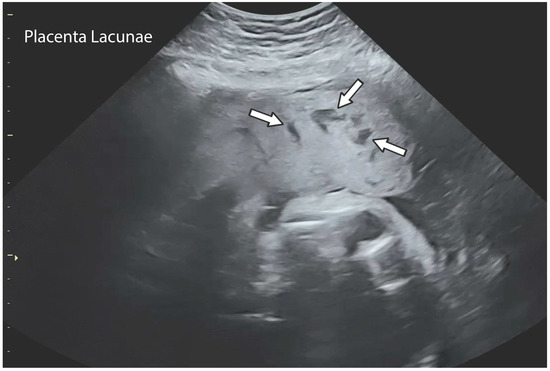

| Characteristics | Placental Lake | Placental Lacunae |

|---|---|---|

| Sonographic appearance | Anechoic area surrounded by normal tissue | Anechoic area surrounded by normal tissue |

| First ultrasound appearance | First trimester of pregnancy | Second trimester |

| Location | Areas of low villous density, under fetal plate, marginal areas | Distortion of placental lobular development around the prior uterine scar |

| Blood flow | Low volume or varying velocity | High volume and high velocity |